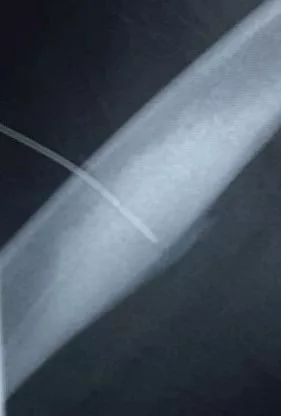

术中,影像引导射频穿刺

术中,劳永锵及潘海文凭借精湛的技术及丰富的手术经验,不断调整穿刺方向,精准直达病灶。在医疗设备科、麻醉科、放射科等各学科的配合,手术顺利完成。

此为横切面视角